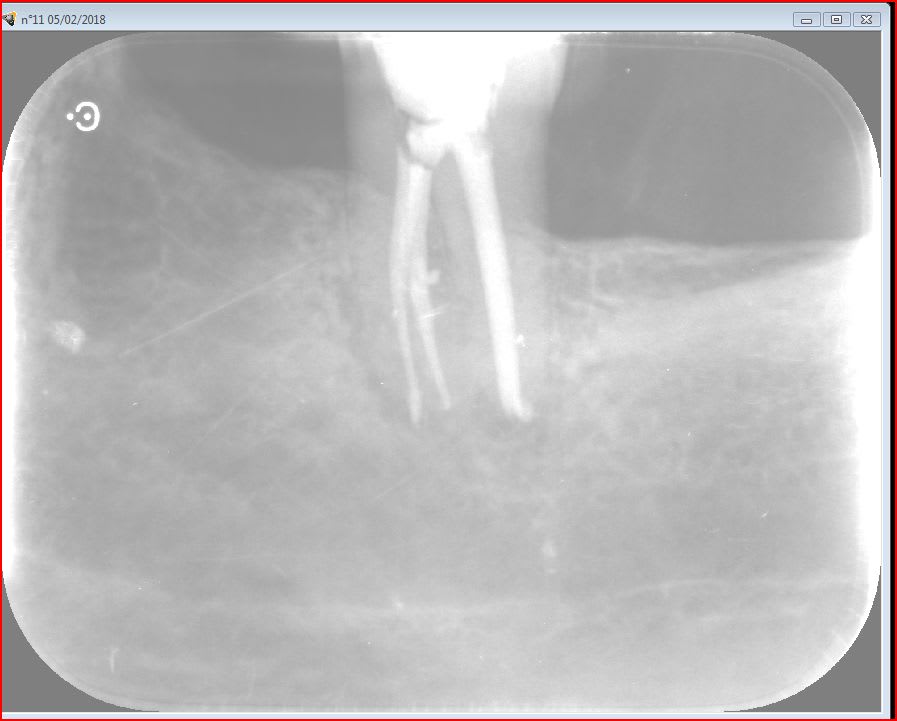

05/02/2018 à 11h23

37

apres une endo de sauvage ,bien bourrée au compactor , 1 petit aller retour pour cette 37 .

pratique pour detartrer la face distale :-))

je vous tiens au courant .